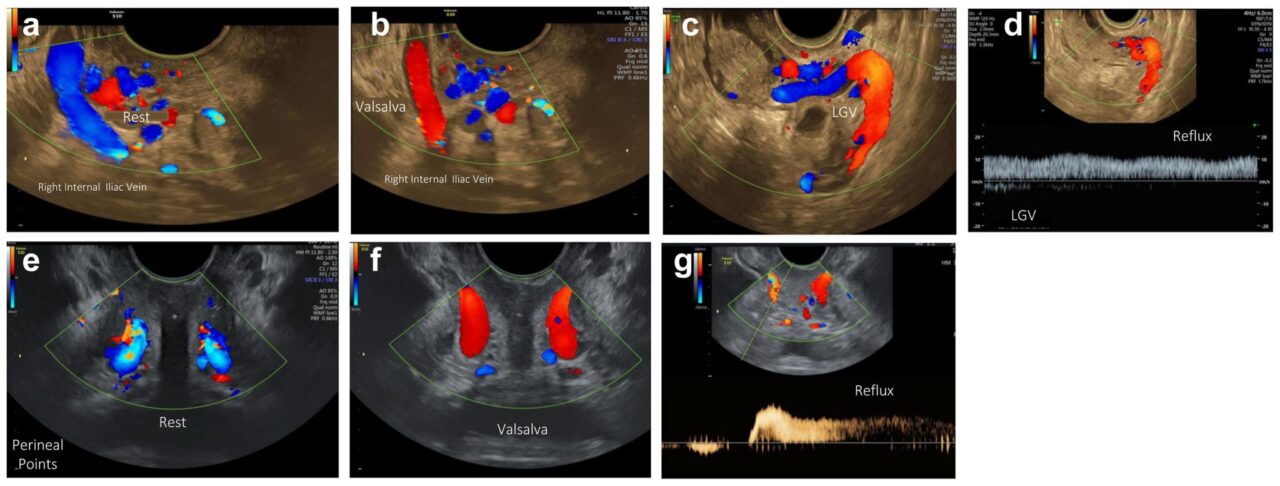

“We should all recognize the importance of precise, patient-centered imaging in the diagnosis and management of Pelvic Venous Disorders (PeVDs) and Chronic Pelvic Pain. The New JVSVL article lays out a Step-by-Step Protocol for Transvaginal Ultrasound (TVUS), offering a reproducible, practical method to assess pelvic veins and venous reflux, key contributors to pain & recurrent varicosities in women.

- TVUS enables real-time assessment of periuterine, perivaginal, gonadal, and iliac veins, with high sensitivity for reflux and post-thrombotic changes

- The protocol emphasizes provocative maneuvers (Valsalva, cough, pelvic floor contraction) to “bring out” hidden reflux that conventional imaging may miss

“Excited to share our ultrasound images with the world! Journal of Vascular Surgery Venous and Lymphatic Disorders

TRANSVAGINAL ULTRASOUND is the apple of our eye when it comes to PELVIC VENOUS DISORDERS, an extremely valuable diagnostic tool!